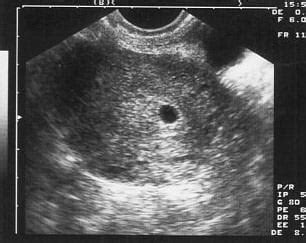

A terhesség korai szakaszában a méhen belül beágyazódott pete körül kialakuló felritkulás, illetve folyadék-felszaporodás látható. A méh ultrahangképén kerek fekete folt jelenik meg, mintha lyukasztóval ütötték volna azt át. A kör alakú folt két legtávolabbi pontjának távolságát mérjük, ami megadja a petezsákátmérőt.

A petezsákot a terhesség korai szakaszában mérik. Körülveszi az embriót és a magzatvizet is. A petezsák a magzat táplálását és fejlődését segíti. Az ultrahangos vizsgálat során a petezsák meglétét keresik a terhesség nagyon korai szakaszában, ez mutatja meg, hogy a teherbeesés megtörtént. Általában már az ötödik hét körül látható a petezsák.